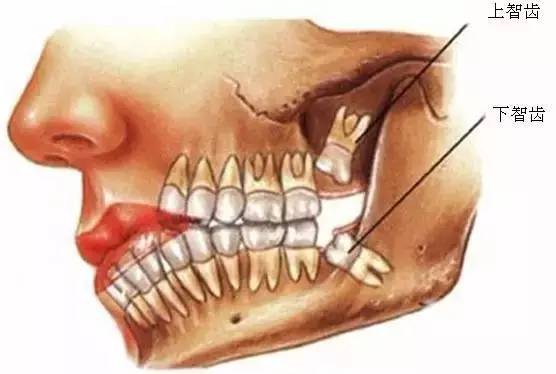

口腔醫(yī)院牙醫(yī)表示,智齒這個(gè)磨人的小妖精,簡(jiǎn)單的說就是人類演化過程的棄兒。觀察古人類和其他靈長(zhǎng)類的頜骨,會(huì)很容易發(fā)現(xiàn),他們的頜骨與現(xiàn)代人相比更大,頰舌面寬度更寬,近遠(yuǎn)中向長(zhǎng)度更長(zhǎng)。頜骨空間充足,智齒的生長(zhǎng)方向和咬合關(guān)系一般都比較正常,很少出現(xiàn)現(xiàn)代人智齒阻生的情況,說明頜骨提供的空間跟智齒的萌出狀態(tài)有直接的關(guān)系。

所以,簡(jiǎn)單的說智齒實(shí)際上是人類演化過程中被放棄的生物學(xué)性狀,由于個(gè)體遺傳基因的不同,在這個(gè)性狀的表達(dá)上存在差異,是否萌出智齒以及萌出數(shù)量都因人而異,有人是4顆全部萌出,有人只萌出1顆,也有人1顆智齒也不長(zhǎng)的。

一般來(lái)說, 完全萌出、形態(tài)位置正常、與旁邊牙齒的鄰接關(guān)系正常、且與頜智齒的咬合關(guān)系正常的智齒是不需要拔除的。

該不該拔掉智齒呢?一般,口腔醫(yī)院的牙醫(yī)會(huì)根據(jù)下列幾點(diǎn)理由,主張拔掉智齒: